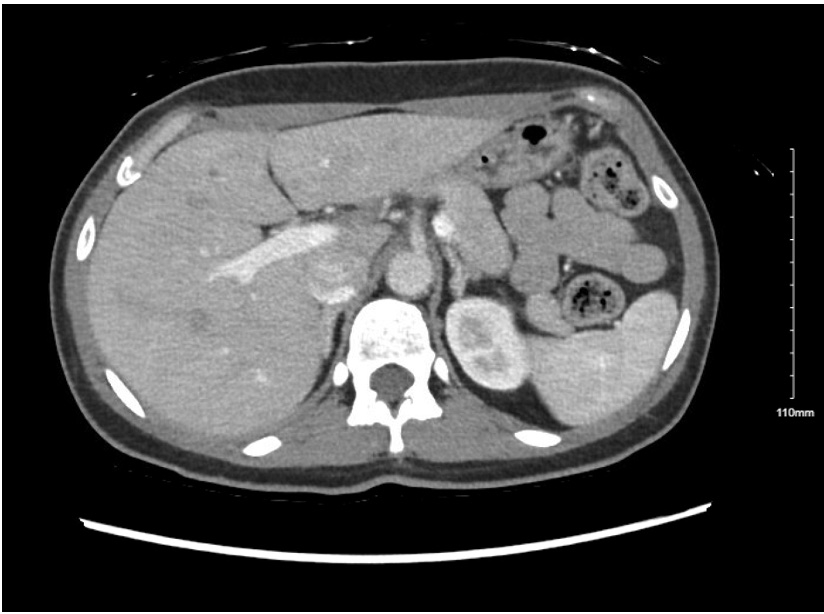

Abstract Body: We present a case of a 40-year-old woman with migraines and a history of pre-eclampsia referred to Complex Hypertension Clinic who experienced recurrent episodes of severe hypertension with associated headaches, palpitations, and a syncopal episode. At presentation, she was on high doses of three antihypertensives. Given the severity of her hypertension and her age, a secondary hypertension work-up was initiated. She had a normal echocardiogram and renal artery duplex ultrasound. During a hospitalization for syncope, she was hypokalemic with a prolonged QTc that normalized with potassium supplementation. A loop recorder was implanted and she was referred for evaluation in electrophysiology clinic, where her loop recorder was negative for arrythmia. In Complex Hypertension clinic, secondary work-up was completed that was negative for OSA and pheochromocytoma. Ambulatory blood pressure monitoring revealed well-controlled home readings, concerning for white coat effect, though she continued to have symptomatic hypertensive episodes. Her aldosterone-to-renin ratio (ARR) was elevated at 62.8, prompting Endocrinology referral, where a repeat ARR was 5.9 with a renin activity of 1.52. Due to discordant results, a saline suppression test and repeat ARRs off losartan were performed (Figure 1). The aldosterone level did not suppress with normal saline infusion. A computed tomography scan [AK1] with adrenal protocol revealed a 1.1 cm x 0.7 cm left adrenal nodule (Figure 2). Adrenal vein sampling was then performed, which showed left-lateralization of aldosterone secretion without contralateral suppression, concordant with a left adrenal nodule. This case highlights the challenges in diagnosing primary aldosteronism. Despite classic signs, such as hypokalemia, biochemical testing was often normal, requiring high clinical suspicion. Specifically, our patient’s repeat renin was not clearly suppressed, which led to the decision to discontinue her angiotensin receptor blocker (ARB) to clarify the diagnosis and accurately interpret ARRs. Furthermore, diagnosis and treatment involved a multidisciplinary team including endocrinology, radiology, electrophysiology, and cardiology. We engaged our patient in shared decision-making and she opted to pursue adrenalectomy. At two-month follow-up, she no longer required antihypertensives, with clinic BP in the 130s/97 and home BP in the 100–110s/70s. Her migraine medications were stopped, and she reported resolution of headaches.